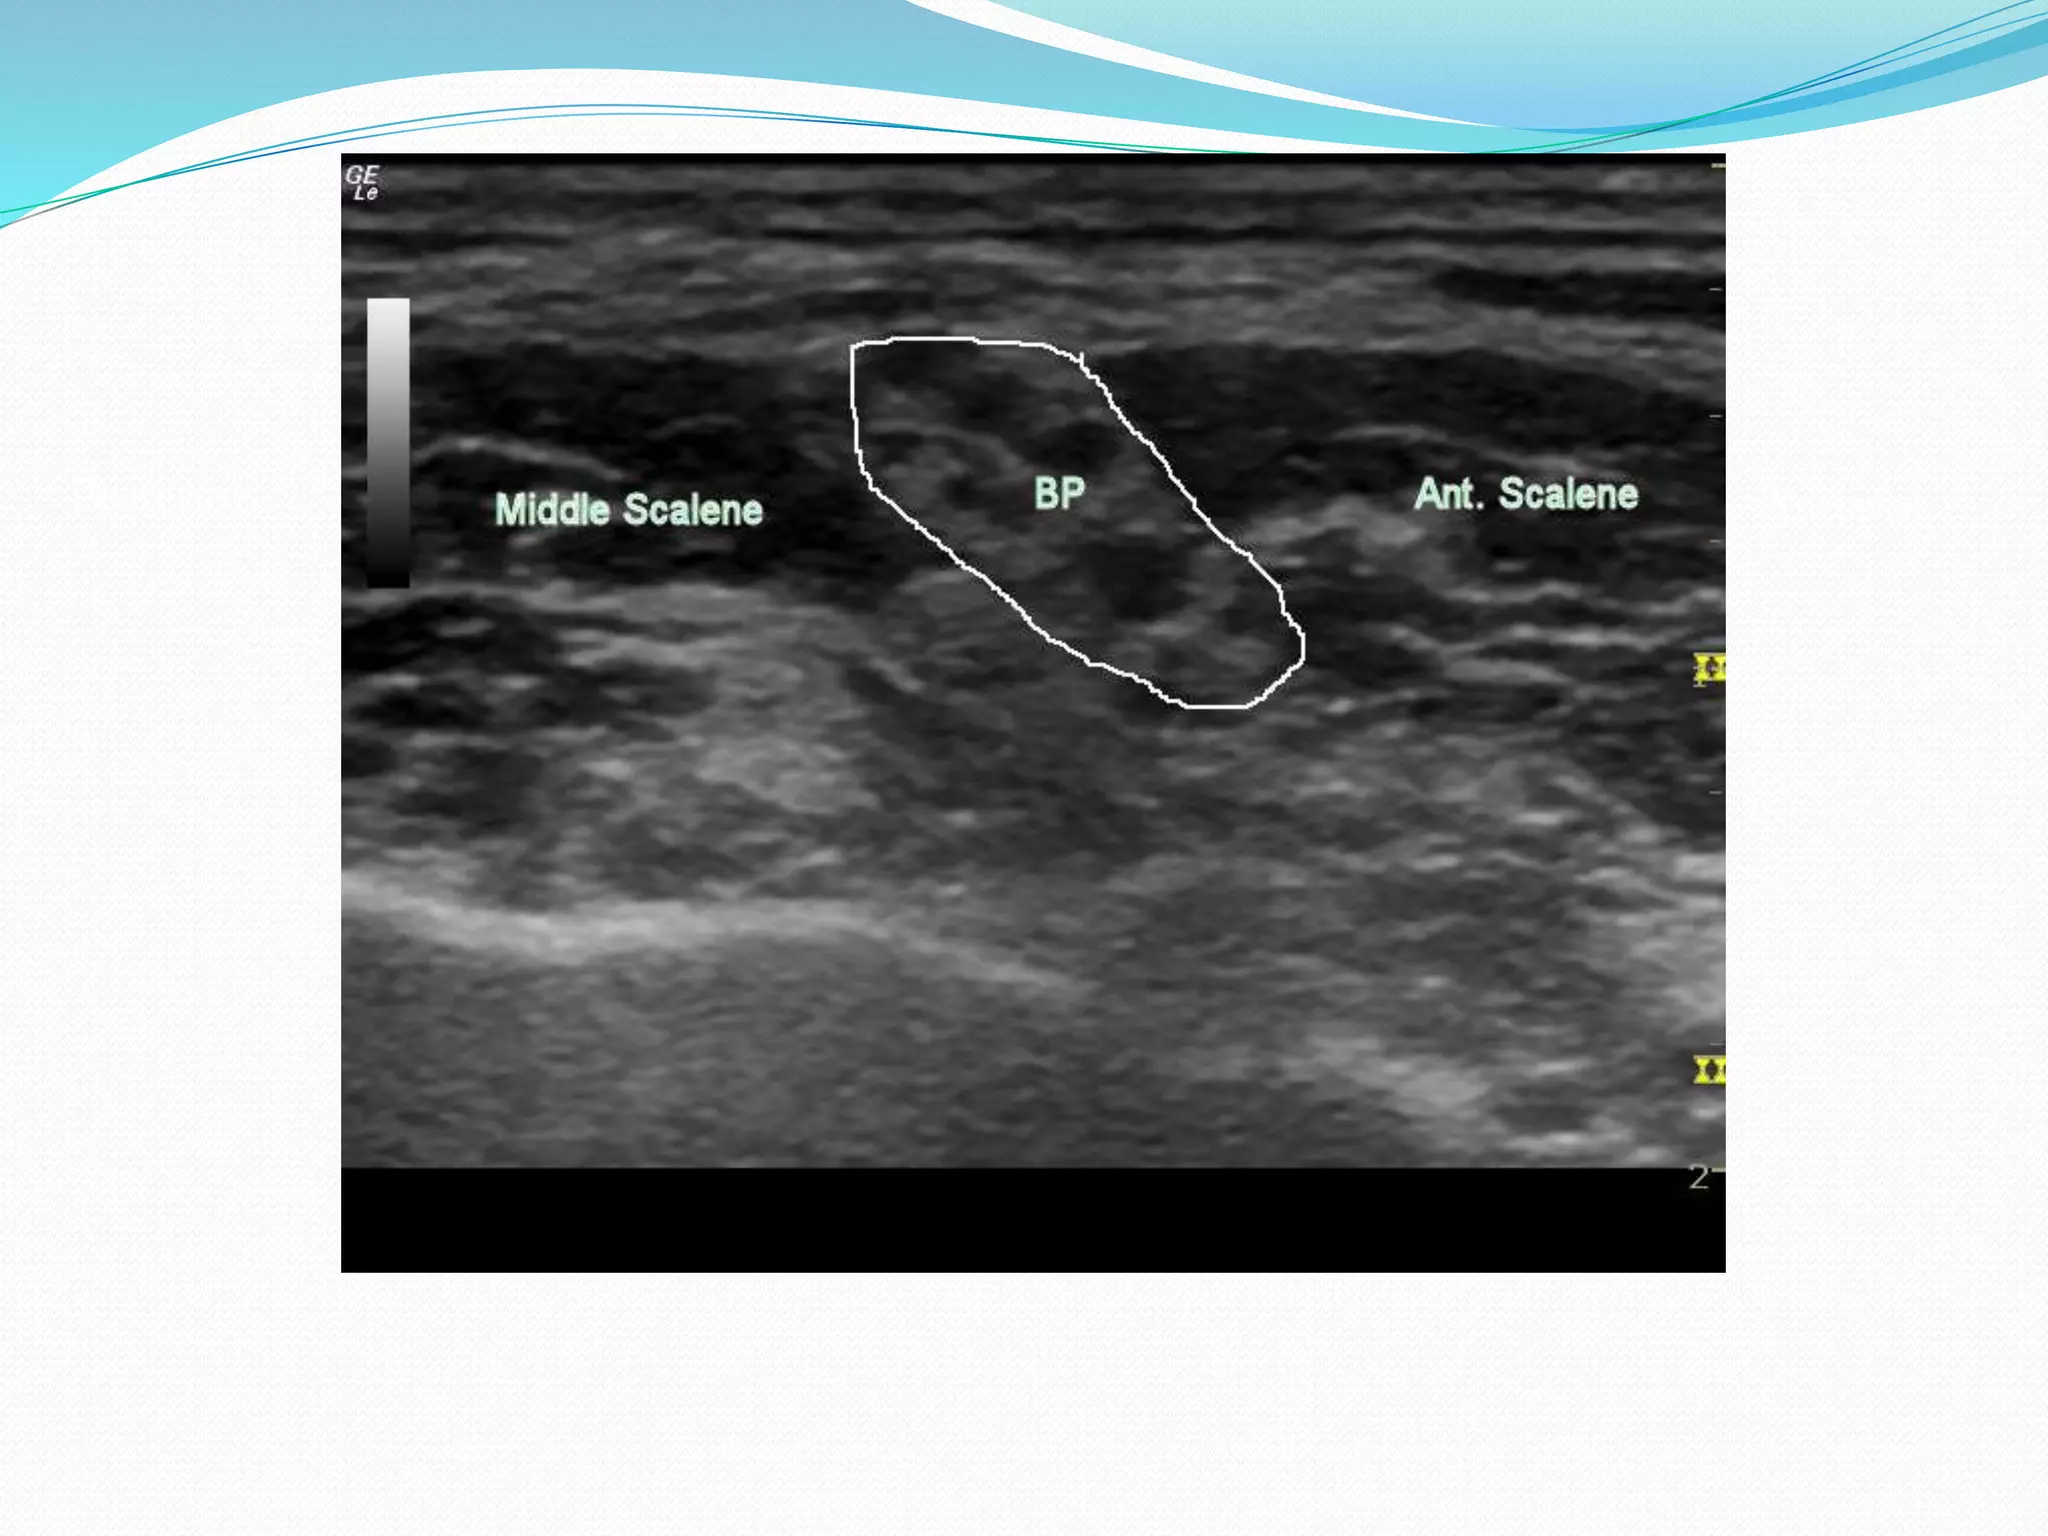

This document provides an overview of brachial plexus anatomy and techniques for brachial plexus nerve blocks. It begins with a description of the brachial plexus formation from cervical and thoracic nerve roots and its branching pattern. Four main approaches for brachial plexus nerve blocks are described: interscalene, supraclavicular, infraclavicular, and axillary. Details are provided on the anatomy and techniques for performing interscalene and supraclavicular brachial plexus blocks. Ultrasound guidance is discussed as an advancement which allows real-time visualization of needle and nerve. Complications are also summarized.